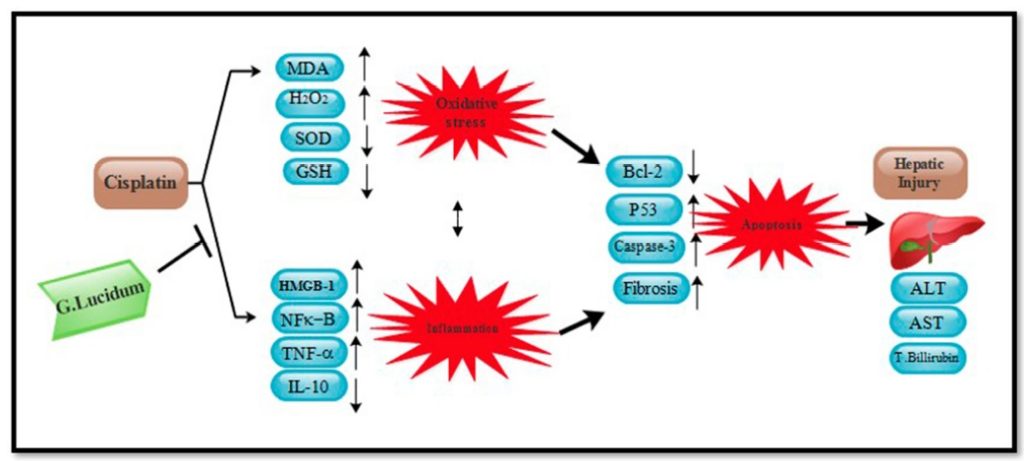

From anti-oxidation, anti-inflammation, anti-apoptosis to the actual performance of reducing liver damage, the researchers have compiled the mechanism of Ganoderma lucidum in inhibiting cisplatin hepatotoxicity into the following diagram for your reference.

Data Source/Drug Des Devel Ther. 2020; 14: 2335-2353.

Figure 6 The mechanism of Ganoderma lucidum in inhibiting liver toxicity of cisplatin